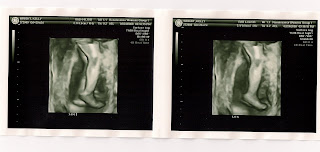

We got to look at another ultrasound and it was amazing to see the level of development this time. We saw the skull, spinal chord, feet, hands, nose, eye sockets (kinda creepy) and some internal organs like the stomach and bladder. Unfortunately, baby Chewie was butt up most of the time and the doc couldn't get a good view of the face so the 3D picture was just legs- good looking stems though, if you ask me.

Here's a few of the ultrasound pics that we scanned: